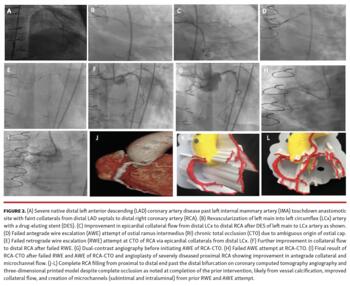

Case 1 (Figure 1 and Figure 2):

a. Buttons of the occluded vein bypass grafts to obtuse marginal (OM) branch, ramus intermedius (RI) and right coronary artery (RCA) are readily identified (1Aa-1Ca) and are noted to be anatomically correct when compared to coronary angiography (1Bb). The operator chose not to selectively engage the vein graft to RCA to avoid renal failure from excessive contrast, as it was reported to be occluded from prior angiogram, which is confirmed on CTA and 3D-PM. The occluded vein graft to RCA can be clearly seen below and slightly posterior to the RI occluded vein graft (1Aa).

b. The patent left internal mammary artery (IMA) to mid-segment left anterior descending (LAD) coronary artery is seen (1Ab, 1Bc, 1Cc) along with distal anastamotic site and diffusely diseased native distal LAD (1Ab, 1Bc-1Bd, 1Cc).

c. Ambiguous ostial RI chronic total occlusion (CTO) cap difficult to discern even on 3D-CTA (1Cb) is more easily identified on the 3D-PM (1Ab-1Ac) and precisely identifies the take-off and angulation, along with the distal vessel course from collateral filling (1Ab-1Ac, 1Bf, 1Cb).

d. Proximal RCA-CTO clinical course: proximal RCA-CTO can be seen on initial diagnostic angiogram (1Ba) with left-to-right epicardial collaterals from distal left circumflex (LCx) (1Be). Prior to the CCTA, the patient had a stent placed from his left main into the LCx, which further improved left-to-right epicardial collateral flow to the RCA from the distal LCx (2B, 2C). An ostial RI-CTO PCI was also attempted but failed due to ambiguity of the cap (2D). Next, CTO-PCI was attempted for his RCA, first with retrograde wire escalation (RWE) from the LCx epicardial collaterals (2E), failing but leading to improvement in left-to-right collateral flow (2F). Failed antegrade wire escalation (AWE) attempt of RCA-CTO and subsequent angioplasty of severely diseased proximal RCA are shown in 2H. The final angiogram at completion of the procedure still showed an occluded proximal to mid RCA with improved antegrade microchannel and collateral flow (2I). The CCTA was performed a few weeks after these interventions and unexpectedly showed complete RCA filling past the distal bifurcation (noted on 3D-CTA and 3D-PM). This finding was likely due to the presence of severe vessel calcification along with improved left-to-right and right-to-right collateral flow and from creation of microchannels (subintimal and intraluminal) from the prior failed CTO-PCI attempt.